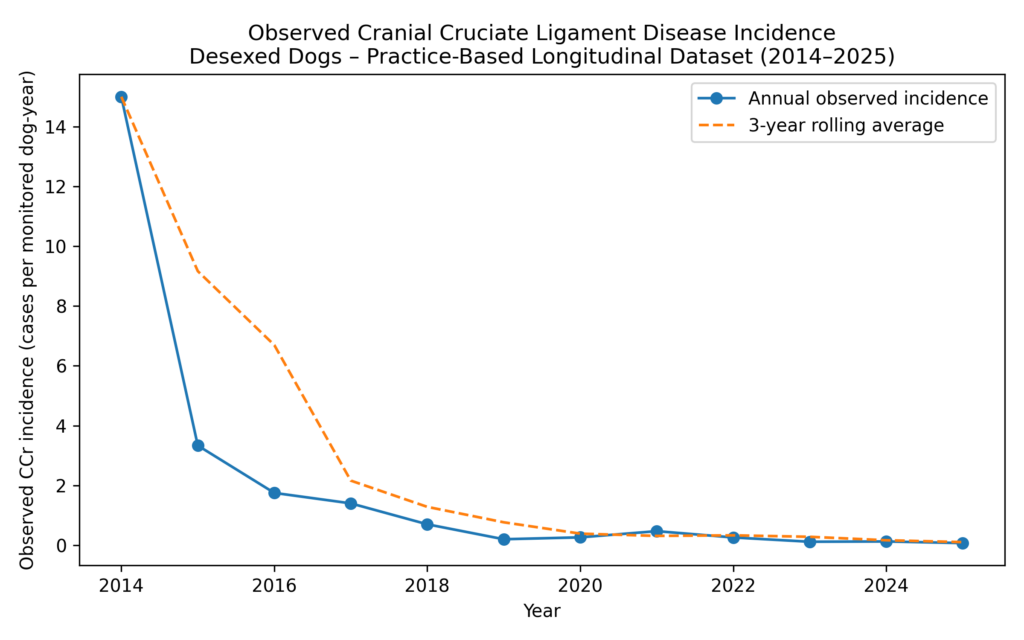

Practice-Based Longitudinal Dataset (2014–2025)

The most complete dataset relates to cranial cruciate ligament (CCr) disease in desexed dogs.

Longitudinal Observational Cohort (2014–2025)

Design

- Single-practice longitudinal observational cohort

- 11-year monitoring period

- Desexed dogs under routine care

- Post-desexing screening integrated into workflow

Observed Findings

Over the 11-year period:

- A sustained downward trend in observed CCr incidence was documented within the monitored cohort

- The decline occurred during the period in which screening and modulation protocols were implemented

Early-year variability reflects small cohort sizes.

The relevant finding is the long-term trend.

Longitudinal Clinical Outcome

Over more than a decade of observation (2014–2025), the practice recorded:

- the number of desexed dogs under active clinical follow-up

- confirmed cases of cranial cruciate ligament rupture

- year-on-year changes within a consistent practice cohort

Observed cranial cruciate ligament disease incidence in desexed dogs monitored within a single veterinary practice (2014–2025).

Data represent observed incidence within the practice cohort. Early-year variability reflects small cohort sizes. The clinically relevant finding is the sustained downward trend over time.

What the Data Shows

The longitudinal data demonstrate:

- a sustained reduction in confirmed CCr disease incidence over time

- this reduction occurring despite an expanding monitored population

- a consistent downward trend when viewed as a rolling average

Early-year variability reflects small cohort sizes and is expected in practice-based datasets.

The clinically meaningful signal is the long-term trend, not isolated annual values.

How to Interpret the Graph

Rates are presented as observed incidence within the monitored cohort, not population risk estimates.